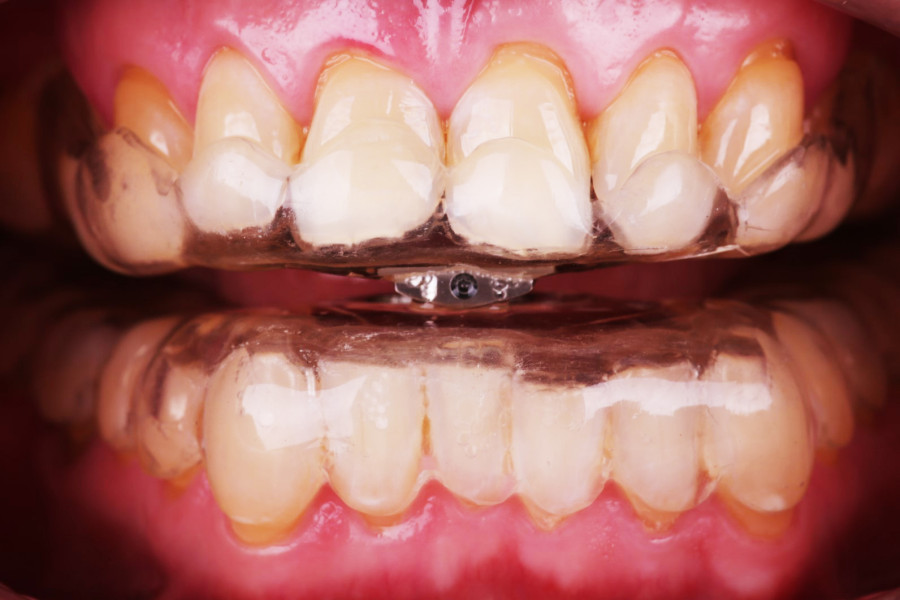

Aparat składa się z dwóch szyn wzajemnie połączonym ze sobą za pomocą rygla, który wysuwa żuchwę względem szczęki do przodu otwierając drogi oddechowe.